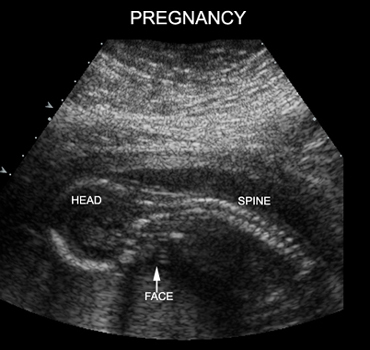

15 Weeks Intrauterine Pregnancy |

15 Weeks Intrauterine Pregnancy |